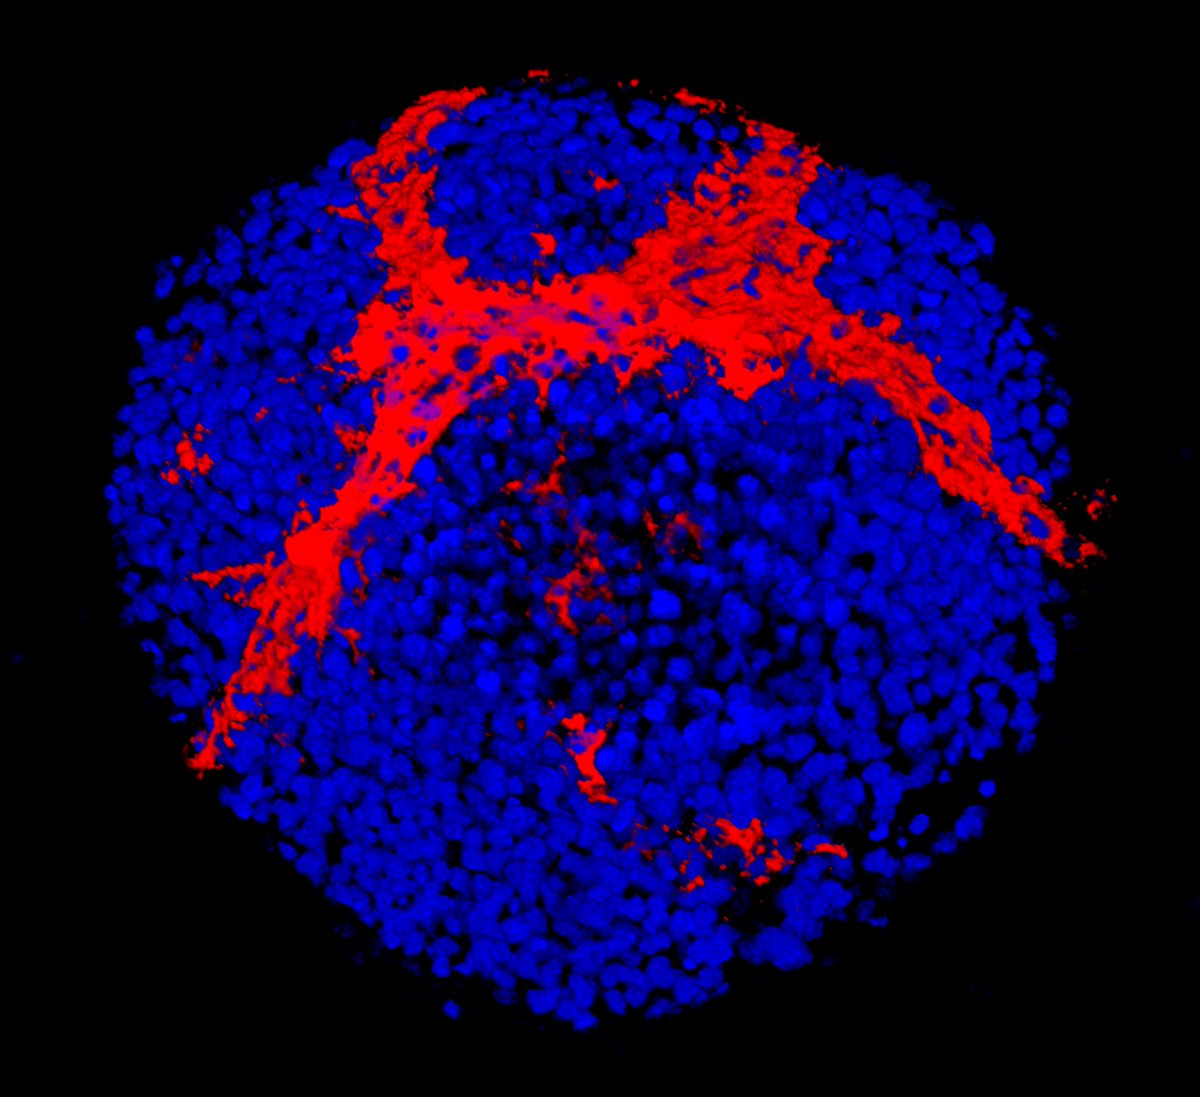

Neuronal microscopy for cell behavioural examination and manipulation.

Single cell analysis is finding rectangluar cells in the European project REVEAL. Experiment Kiran Padmanabhan, deep learning analysis at CEA-Leti. Thanks to #cellpose + #TrackMate on lens-free microscopy phase images IPRASENSE - Cell Culture Monitoring Instruments.

European project @REVEAL_H2020is measuring dry mass of millions of cells. Experiment Kiran Padmanabhan, deep learning analysis at CEA-Leti. Thanks to Cellpose + #TrackMate on lens-free microscopy phase images IPRASENSE - Cell Culture Monitoring Instruments.